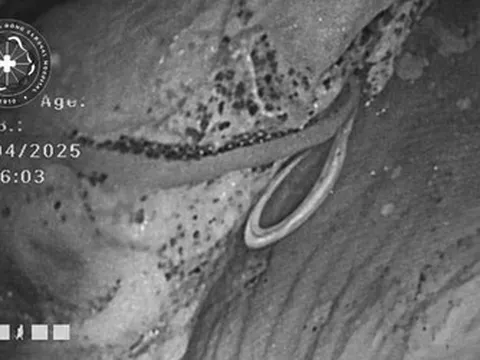

Bác sĩ bệnh viện K thao tác điều khiển Robot Davinci thế hệ Xi thực hiện phẫu thuật cho bệnh nhân ung thư thận

Ngày 03/08/2022, ca phẫu thuật được thực hiện với sự tham gia của PGS.TS. Phạm Văn Bình - Phó Giám đốc Bệnh viện và ThS.BS CKII Đỗ Anh Tuấn - Trưởng khoa Ngoại tiết niệu cùng các bác sỹ trong khoa: BSCKII.ThS. Nguyễn Việt Dũng - Phó Trưởng khoa Ngoại tiết niệu; ThS.Trần Đình Tân - Phó Trưởng khoa Ngoại bụng 1; BS. Đoàn Hữu Đạt - Khoa Ngoại tiết niệu đã thực hiện thành công ca phẫu thuật cho bệnh nhân H.

Khối u kích thước khoảng 6cm ở cực trên của thận trái, đây là vị trí tổn thương tương đối thuận lợi, vùng rốn thận chưa có xâm lấn vì vậy ca phẫu thuật diễn ra rất thuận lợi, đặc biệt với các bác sỹ kinh nghiệm lâu năm của Bệnh viện K.